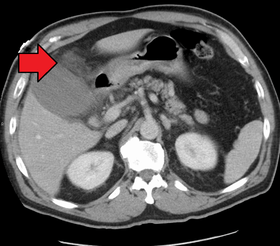

![]() Acute cholecystitis as seen on CT. Note the fat stranding around the enlarged gallbladder. | |

Right upper quadrant abdominal ultrasound is most commonly used to diagnose cholecystitis.[1][22][23] Ultrasound findings suggestive of acute cholecystitis include gallstones, fluid surrounding the gallbladder, gallbladder wall thickening, dilation of the bile duct, and sonographic Murphy's sign.[2] Given its higher sensitivity, hepatic iminodiacetic acid (HIDA) scan can be used if ultrasound is not diagnostic.[2][13] CT scan may also be used if complications such as perforation or gangrene are suspected.[13]